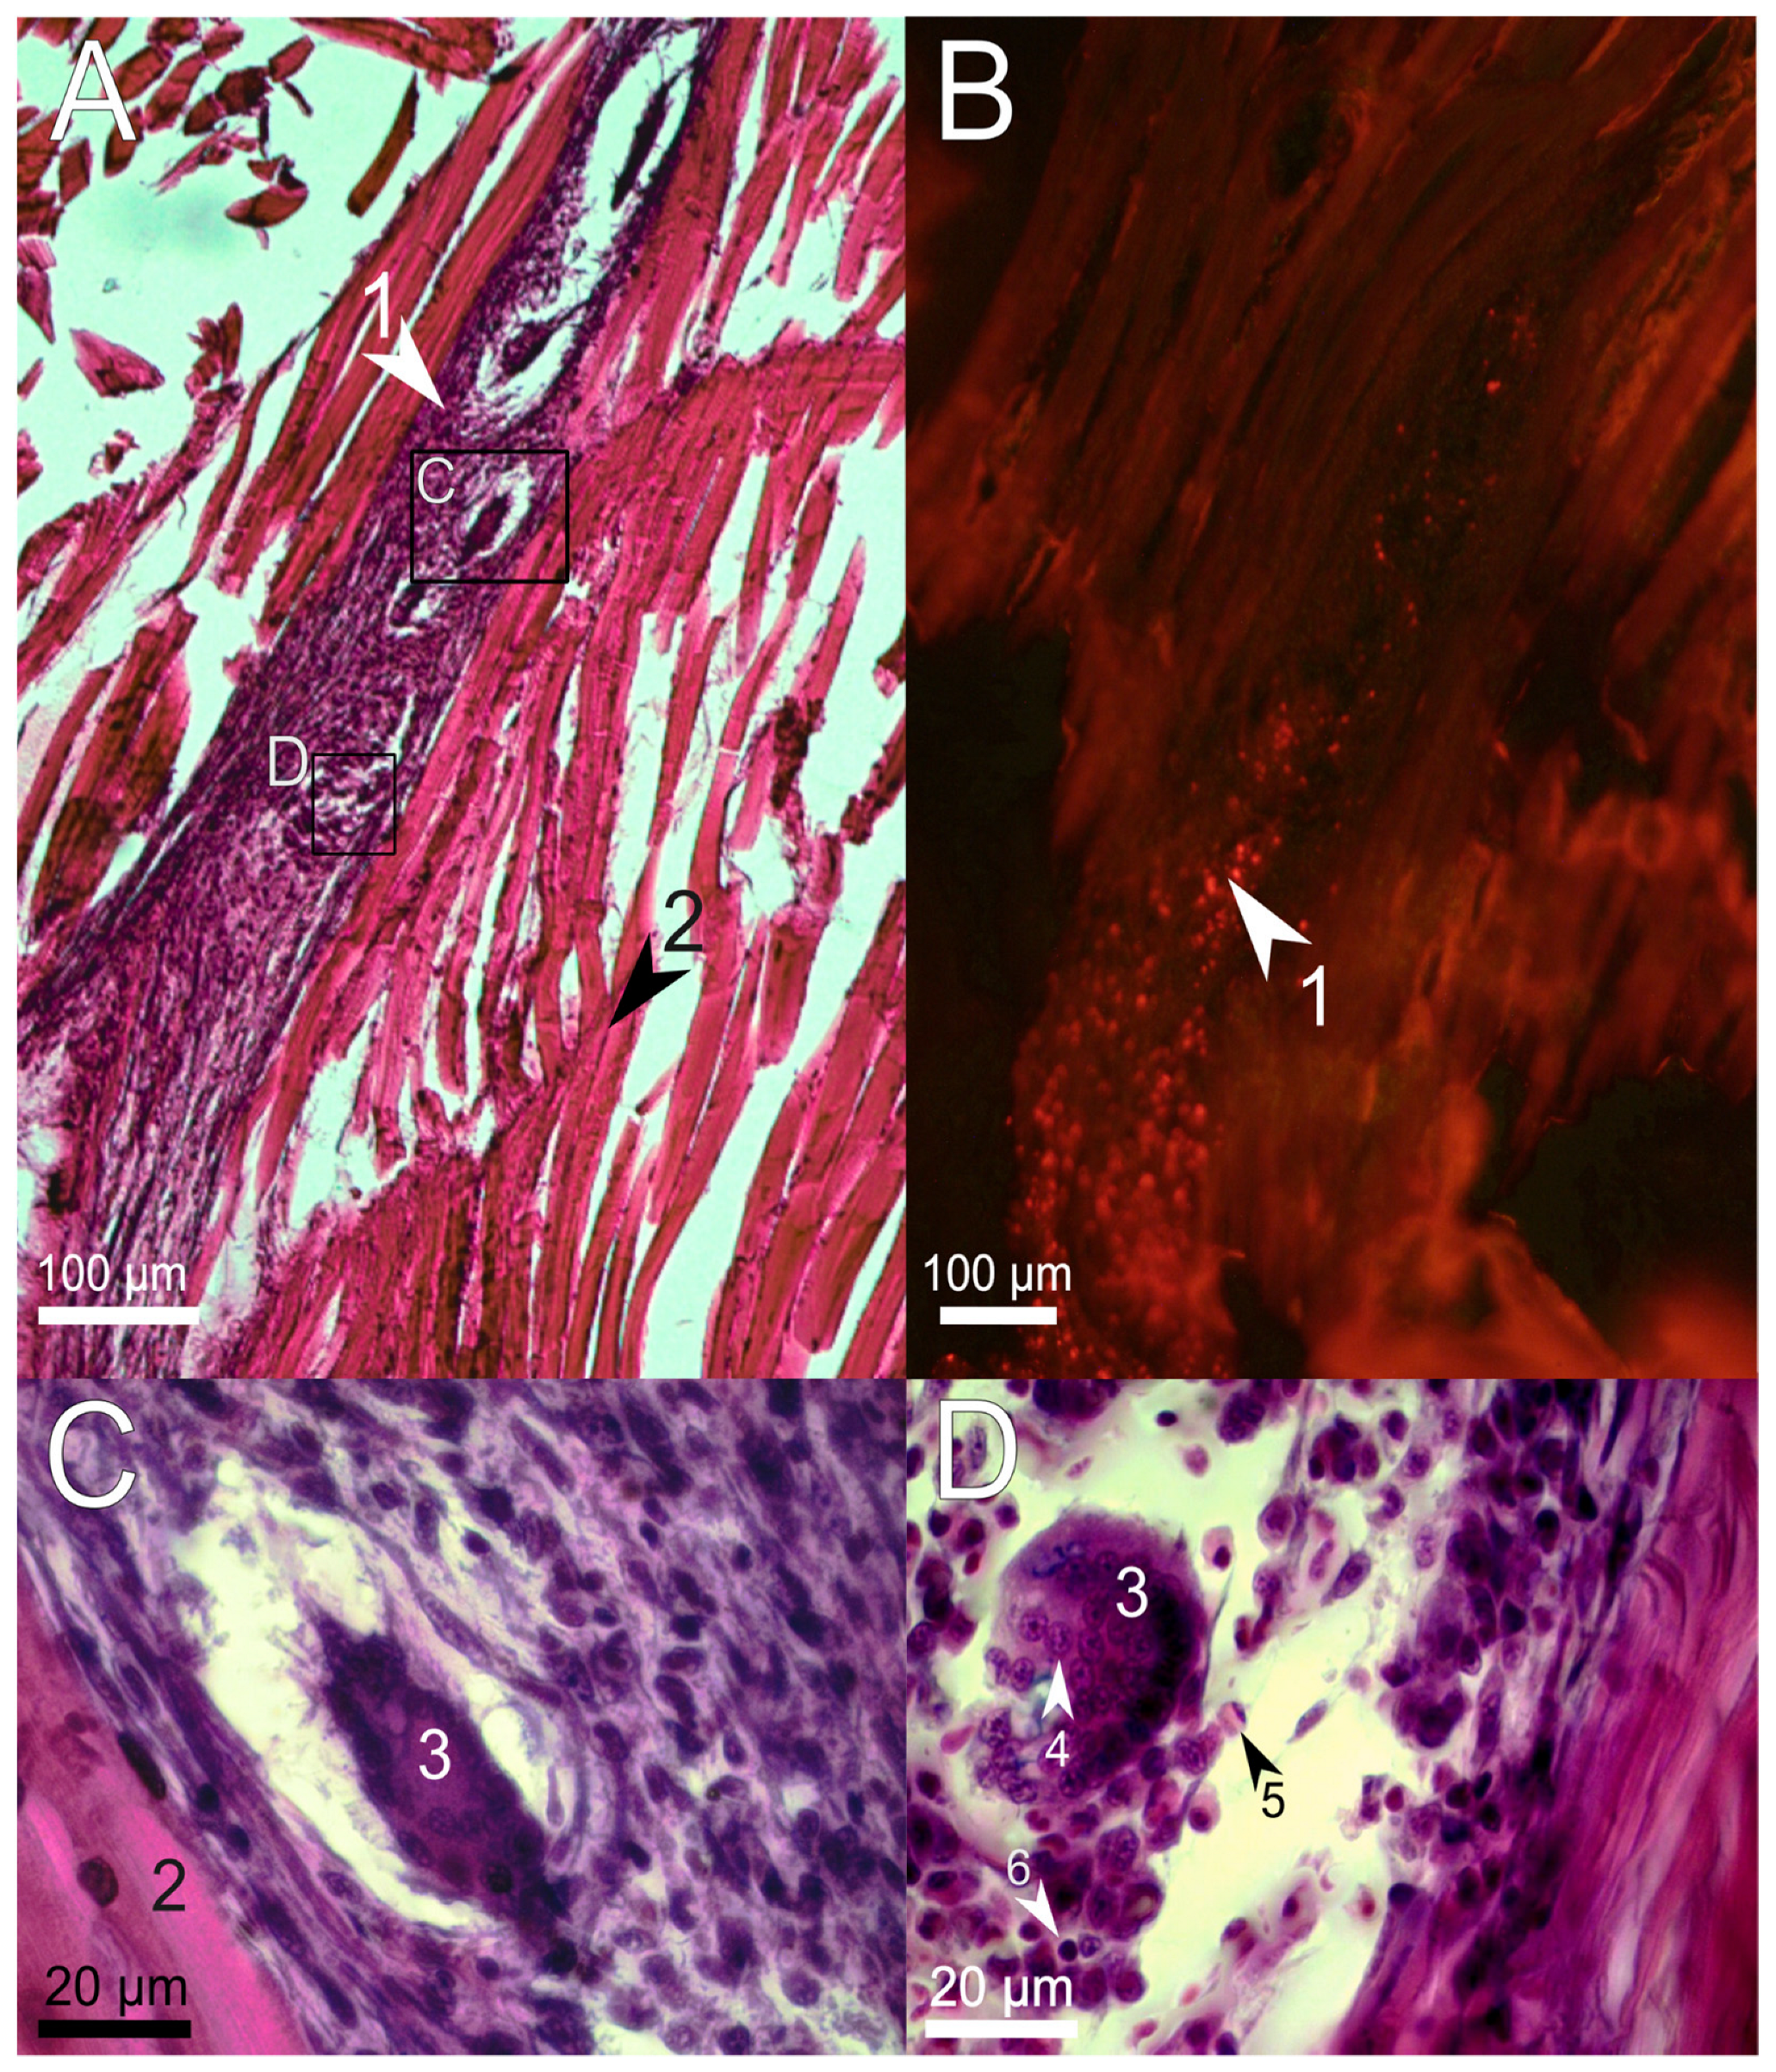

3.2. Histological Examination of the Immune Response to the Implanted Hydrogel in Fish Muscles